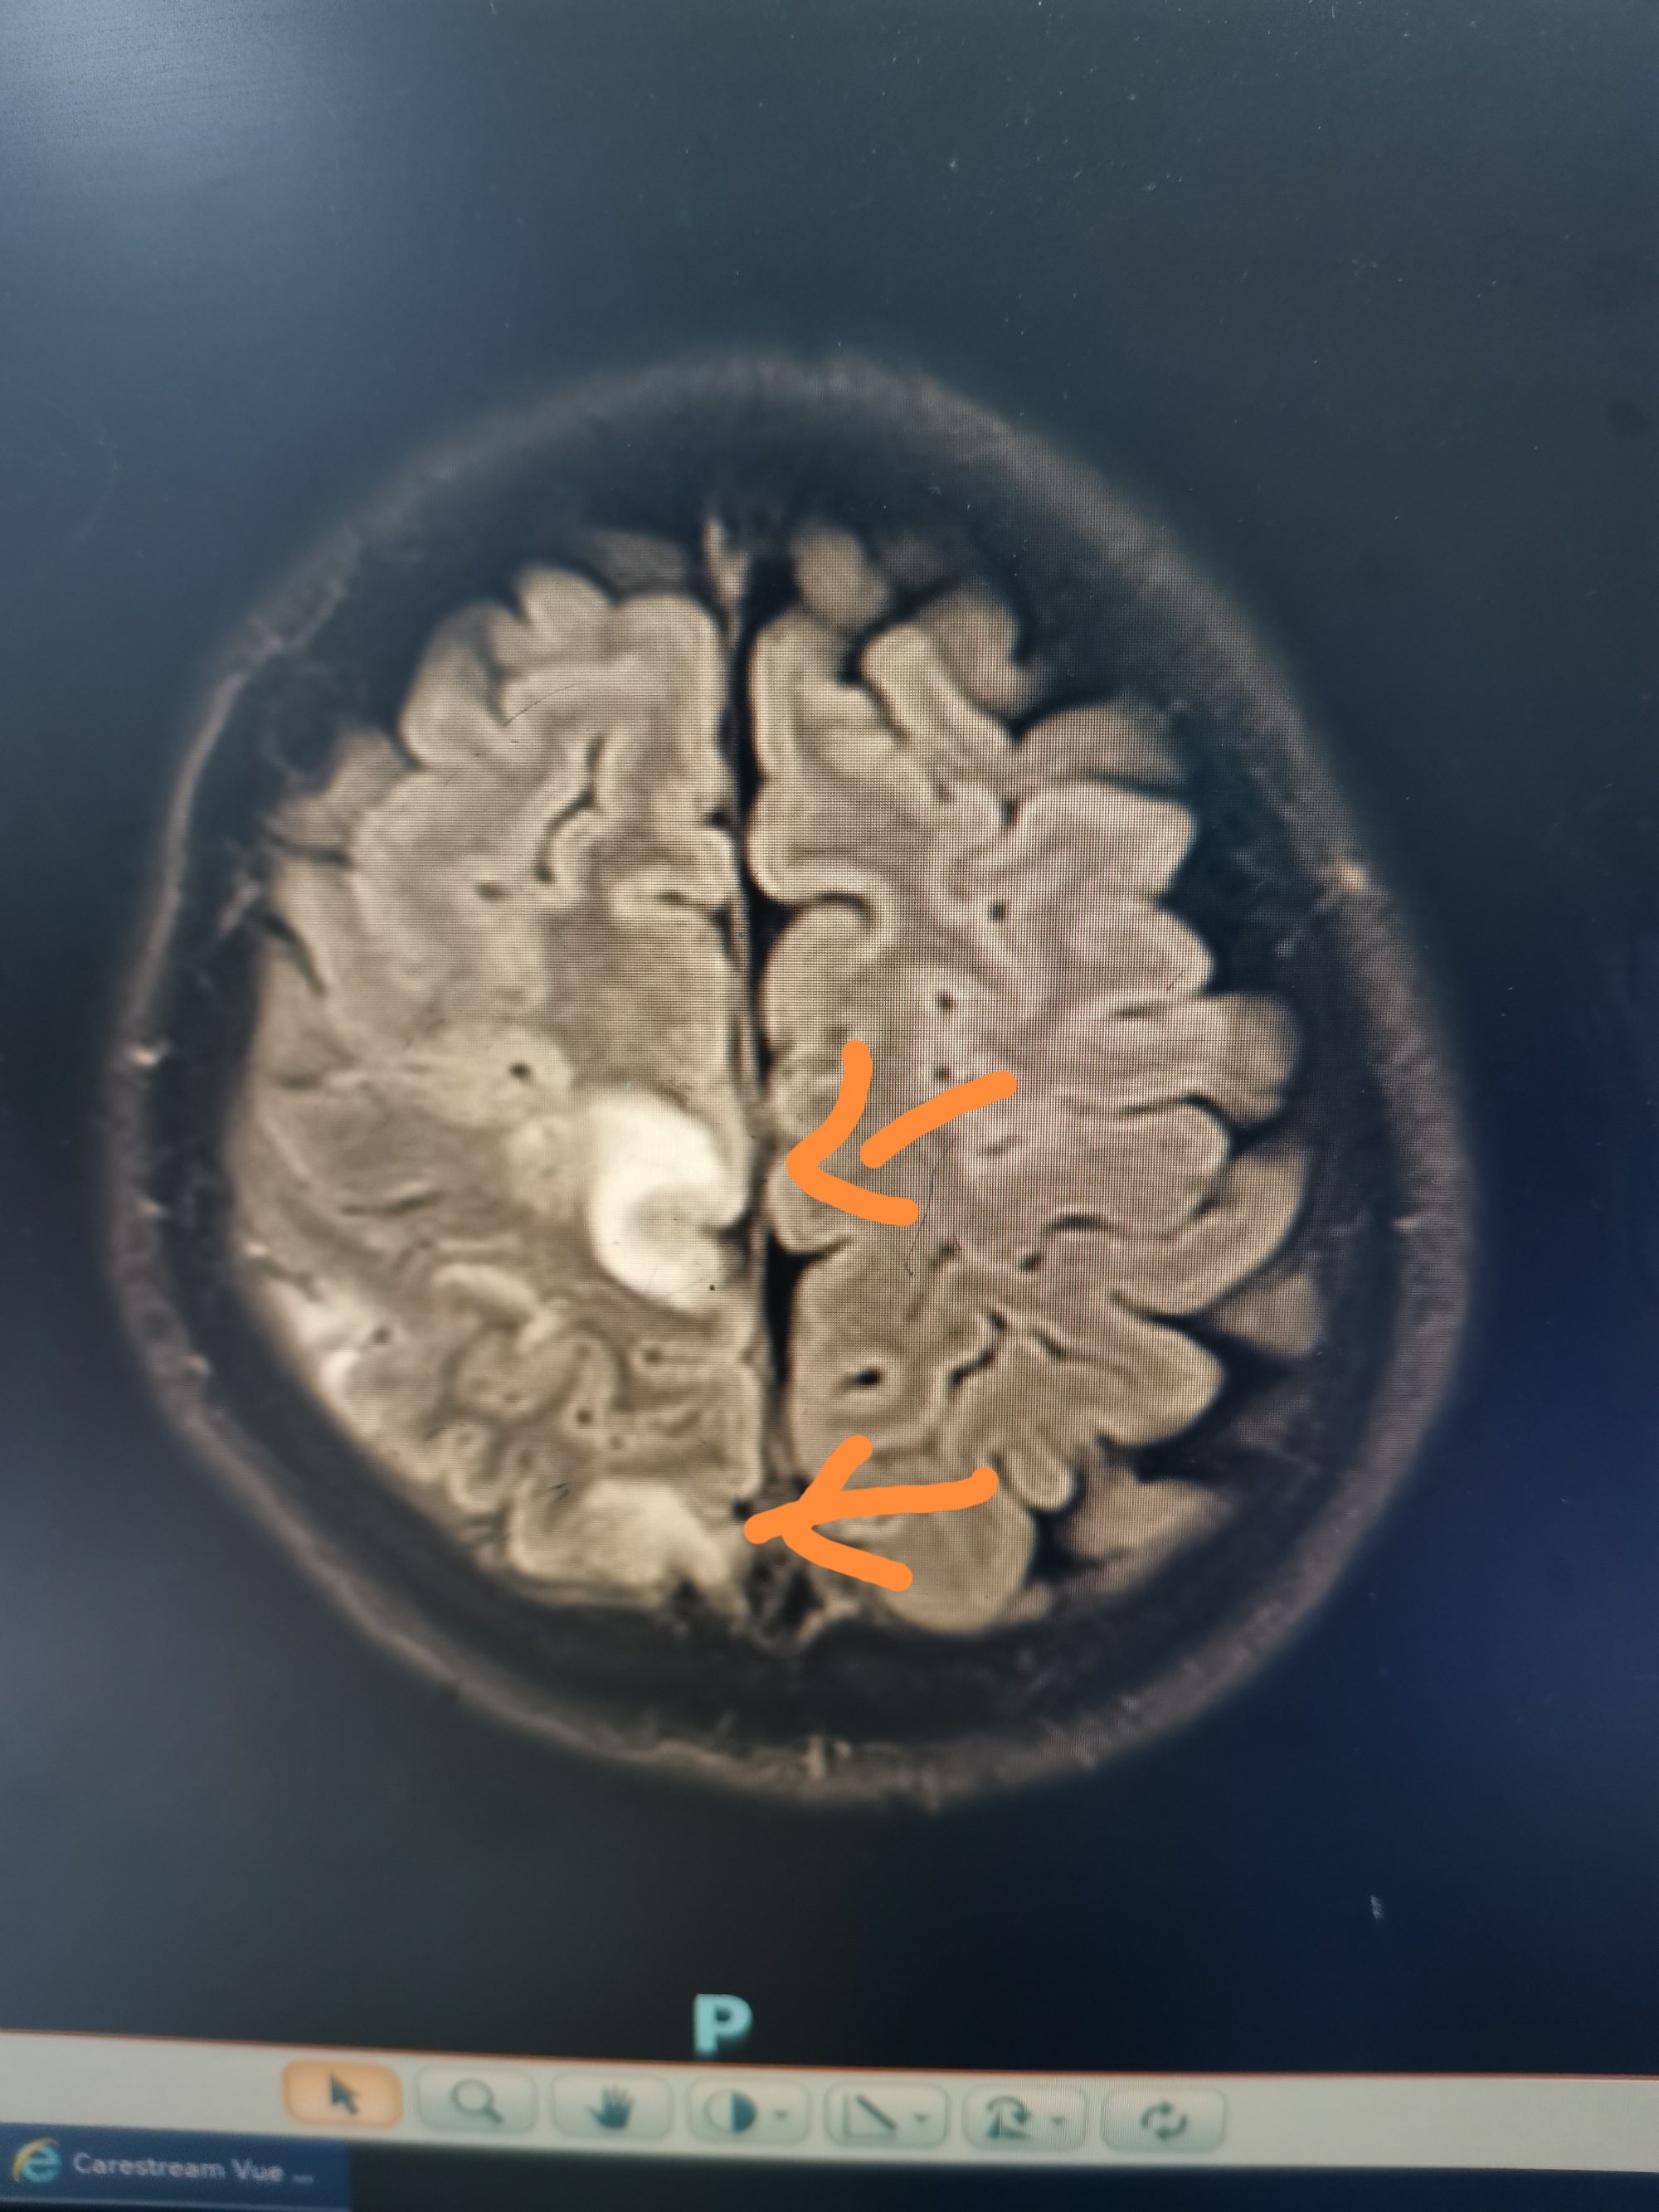

入院后急查头颅磁共振发现顶叶又新发两个病灶。

磁共振发现顶叶又新发两个病灶

DWI考虑新发病灶为脑梗死,考虑该梗塞病灶位于运动皮层导致患者右下肢完全偏瘫。

磁敏感成像考虑首发病灶为出血。

增强显示矢状窦长节段充盈缺损,D-2聚体大于正常上限5倍以上。我科诊断考虑上矢状窦血栓形成伴多发多次脑梗死伴出血。